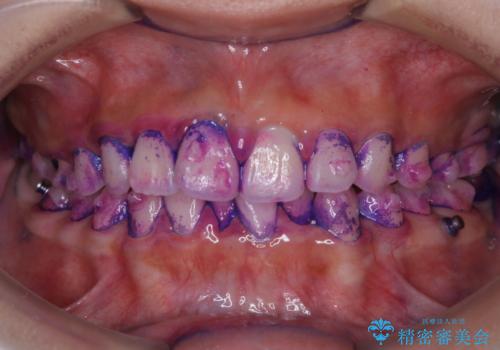

口腔内にはたくさんの細菌がいるため、ヌルヌルとしたプラーク(歯垢)が自然に歯の表面に付きます。

このプラーク(歯垢)にはたくさんの細菌が潜んでおり、虫歯や歯周病・口臭などの最大の原因です。そのため、毎日の歯磨きでプラーク(歯垢)をキレイに取り除くことが、健康な歯を保つためには欠かせません。

しかし、プラークは歯の色と似ているため、見ただけでは付着しているかどうかがハッキリとは分かりません。

染め出し液を使ってプラークを染め出すことにより、普段の歯みがきで磨き残している場所を目で確かめることができます。

日々の歯磨きを上達するには、まずどこが磨けていないか認識することが大切です。